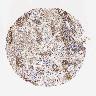

CERVICAL CANCER - Protein expressioni

A mouse-over function shows sample information and annotation data. Click on an image to view it in a full screen mode. Samples can be filtered based on level of antibody staining by selecting one or several of the following categories: high, medium, low and not detected. The assay and annotation is described here.

Note that samples used for immunohistochemistry by the Human Protein Atlas do not correspond to samples in the TCGA dataset.

Antibody stainingi

Antibody staining in the annotated cell types in the current human tissue is reported as not detected, low, medium, or high, based on conventional immunohistochemistry profiling in selected tissues. This score is based on the combination of the staining intensity and fraction of stained cells.

Each image is clickable and will lead to virtual microscopy that enables deeper exploration of all samples and also displays staining intensity scores, fraction scores and subcellular localization as well as patient and tissue information for each sample.